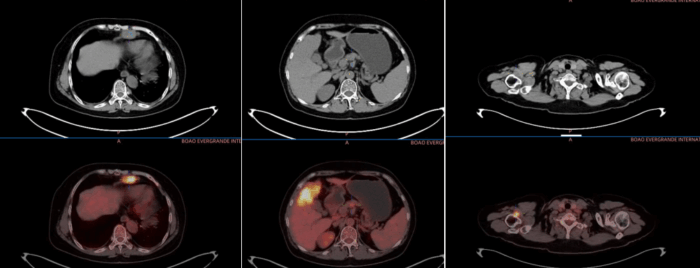

影像图

瑞金海南医院副院长、普外科主任医师金佳斌迅速组织与上海瑞金医院的多学科讨论。上海瑞金医院舟山分院院长、放射科主任医师缪飞,上海瑞金医院放射科主治医师朱乃懿和瑞金海南医院放射科主任医师唐永华通过精准读片确定了肿瘤范围;上海瑞金医院核医学科主任医师林晓珠通过核医学检查评估肿瘤全身转移情况;瑞金海南医院副院长、普外科主任医师金佳斌,普外科主任医师王艳良,普外科副主任医师赵良超经评估认为,虽然肿瘤较大但仍有切除可能;上海瑞金医院病理科主任医师杨晓群和瑞金海南医院病理科主治医师乔坤朋的确诊更是关键——这是一种特殊的EB病毒相关性肝内胆管癌,且免疫组化显示PD-L1高表达,这为后续治疗指明了方向。

三个月后,奇迹开始显现,肝脏肿瘤明显缩小,转移淋巴结显著减小,上臂皮下的转移灶几乎消失。